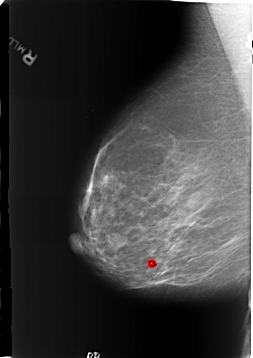

B_3186_1.RIGHT_MLO

RIGHT_MLO LINES 5720 PIXELS_PER_LINE 4040 BITS_PER_PIXEL 12 RESOLUTION 50 OVERLAY

FILE: B_3186_1.RIGHT_MLO.OVERLAY

TOTAL_ABNORMALITIES 1

ABNORMALITY 1

LESION_TYPE CALCIFICATION TYPE LUCENT_CENTERED DISTRIBUTION N/A

ASSESSMENT 2

SUBTLETY 4

PATHOLOGY BENIGN

TOTAL_OUTLINES 1

BOUNDARY